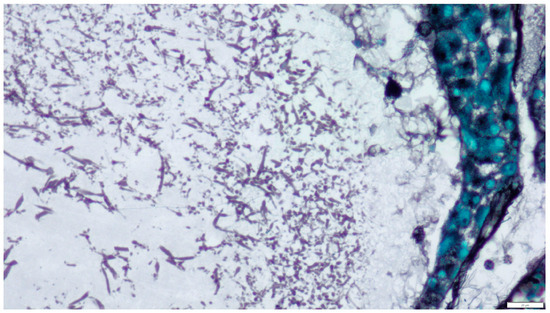

- Stained preparations: smears, histopathological preparations;

- Other techniques include fluorescence, immunohistochemistry, immunofluorescence, and in situ hybridization. Immunohistochemical tests with monoclonal antibodies (WF-AF-1, EB-A1), immunofluorescence, and in situ hybridization are also used in diagnostics to determine the genus and species, especially in cases where it is not possible to culture fungi [3,13,14,16].